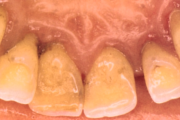

Krooniline parodontiit

Krooniline parodontiit on mikroobide poolt põhjustatud hammaste tugikudede põletik, mille tulemusena tekib progresseeruv alveolaarluu (nähtav röntgenograamil) ja periodontaalligamendi destruktsioon, igemetaskute moodustumine, igeme retsessioon või mõlemad kahjustused kombineeritult. Loe edasi »

- puudulik suuhügieen (5)

- igemepealne hambakivi (5)

- vahed hammaste vahel (5)

- halb hingeõhk / suu haiseb (12)